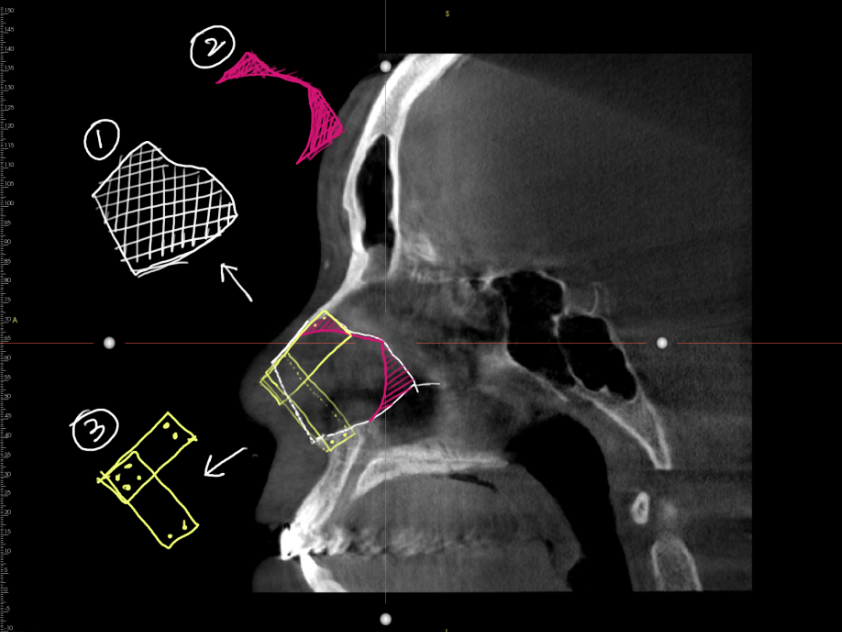

In the first operation, the nasal septum and alar cartilage were reconstructed using autologous rib cartilage.

A septal extension graft was performed to lower the nasal tip and correct the contracted appearance.Under the depressed nasal skin, autologous dermis and ear cartilage were transplanted to rebuild the soft tissue layer.

A portion of the rib cartilage was preserved for the second-stage surgery to ensure long-term support and contour stability.

The second surgery focused on correcting nostril asymmetry and depressed nasal skin using the preserved rib cartilage.

The depressed areas were reinforced with additional rib cartilage, achieving a natural nasal contour and improved symmetry.